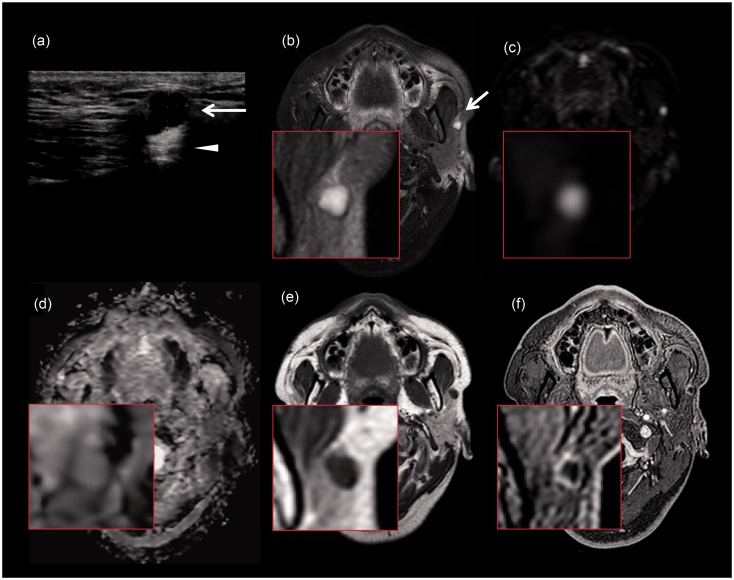

A 34-year-old man found a mildly tender preauricular mass. Ultrasonography revealed an anechoic mass in the superficial lobe of the parotid gland. Magnetic resonance imaging showed thin ring-like contrast enhancement and homogenously high intensity on T2-weighted images. The mass was resected due to its rapid growth. The cystic lesion contained keratine-like material and a stratified squamous epithelium without granular layers, which was consistent with keratocystoma.